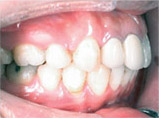

向外暴出

牙齒向外暴出藉由矯正得到適當的改善:

Before

After